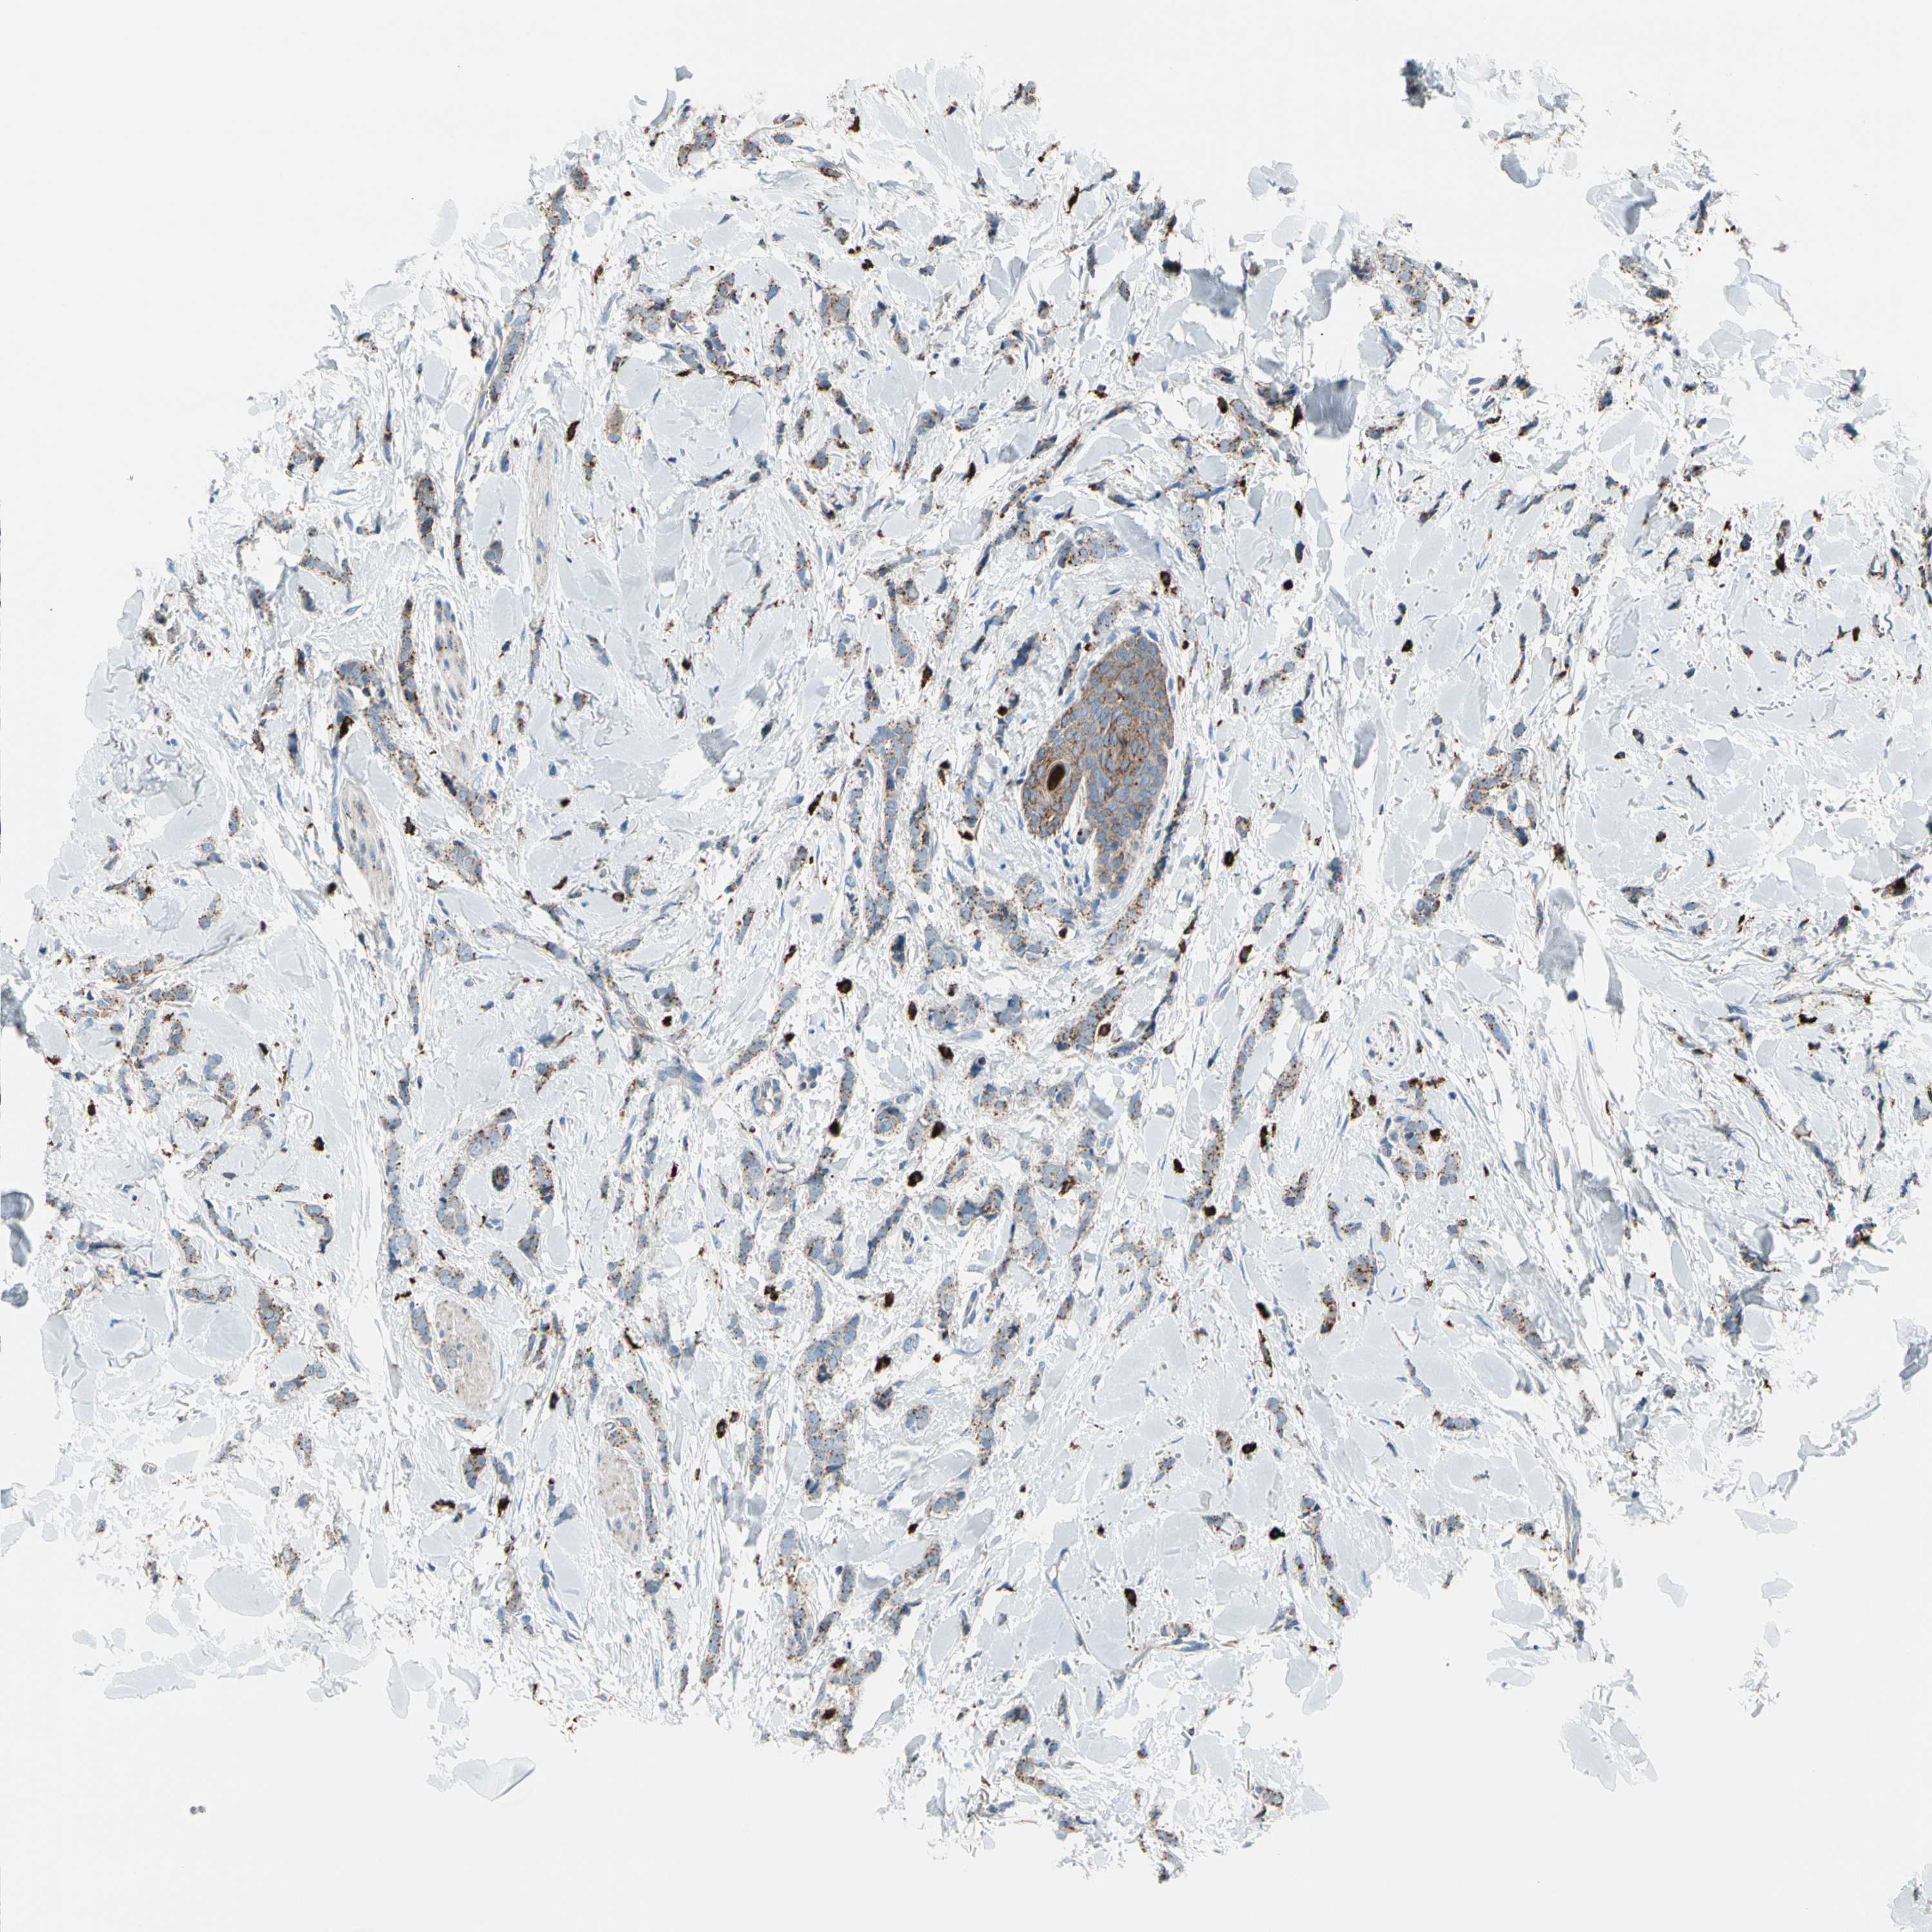

CANCER BREAST CANCER Show tissue menu

BRCA TCGA BRCA VALIDATION PROTEIN EXPRESSION

Breast cancer

Human cancer

Breast invasive carcinoma